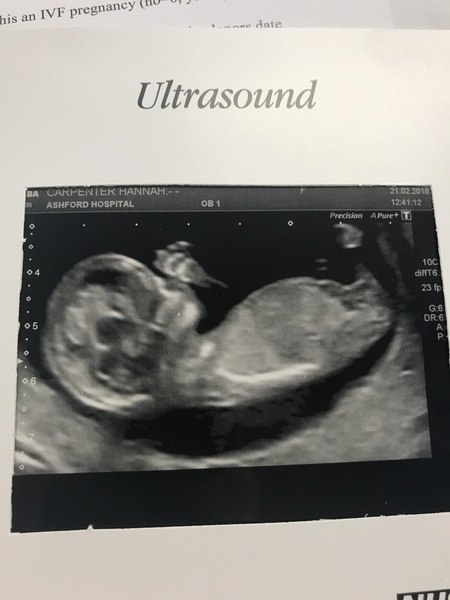

My 12w scan image is here.... any guesses on gender? My scan is a week on Saturday. Cannot. Wait.

Hannahcarp27 · 21/02/2018 19:53

Finally had my 12 week Scan. Dates have moved so EDD 30th August now. I expect I will actually be having a September baby as first DD was 10 days late. Can't believe how clear the scan is. Can see the little hand waving